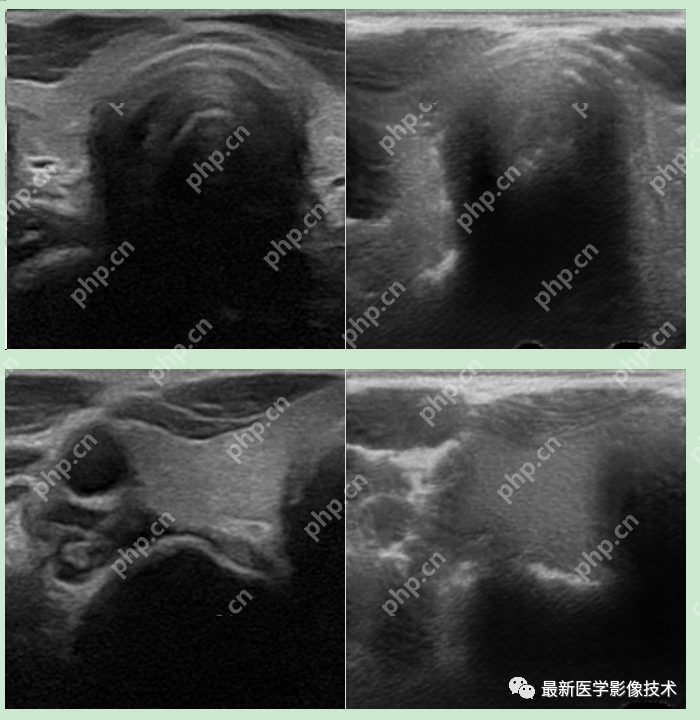

5、验证集部分生成结果

左图为低质量图像,中间为生成的高质量图像,右图为真实的高质量图像。